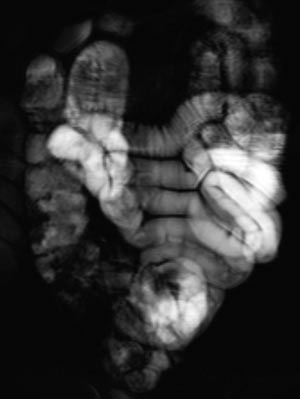

MR-undersøkelser av tynntarm ble tidligere ikke gjort pga. bevegelsesartefakter fra tarmperistaltikken. Optimal MR-fremstilling krever raske sekvenser som alene eller i kombinasjon med peristaltikkdempende medikamenter gir god bildekvalitet. Moderne MR-maskiner bruker ulike nye teknikker som gradientekko og rask spinnekko samt parallell datainnsamling fra flere antenner for å oppnå dette (e-tab 1). Standardsekvenser ved MR av tynntarm er først en rask T2-vektet spinnekkosekvens (SST2WTSE) med et tykt snitt av tynntarmen som gjentas dynamisk. Dette gir god fremstilling av den væskefylte tynntarmen og eventuelle stenoser. Sekvensen kalles også for «MR-fluoroskopi», og bildene likner på konvensjonelle røntgenbilder av tynntarm.

MR av tynntarm med sonde

En viktig forutsetning for radiologisk fremstilling av tynntarmen er at tarmslyngene er utspilt. Hvis tynntarmen har falt sammen, kan patologiske tilstander overses. Én MR-metode innebærer nedleggelse av sonde til tynntarmen og installasjon av væske i denne (1) – (6). Væsken vil vanligvis være tilsatt et stoff som hindrer absorpsjon. Undersøkelsen starter med at pasienten får lagt ned en sonde til proksimale tynntarm på et gjennomlysningslaboratorium. Sonden blir lagt forbi Treitz’ ligament. Den har en ballong distalt som hindrer refluks til ventrikkelen. Deretter fortsetter undersøkelsen på MR-laboratoriet. Pasienten ligger i bukleie i magneten. Sonden kobles til en pose med væske. Væskeinfusjonen starter ved hjelp av manuell installasjon og overvåkes med MR-fluoroskopi (fig 1). Når høyre colonhalvdel er godt væskefylt, stoppes væskeinstallasjonen og man starter de øvrige sekvensene.